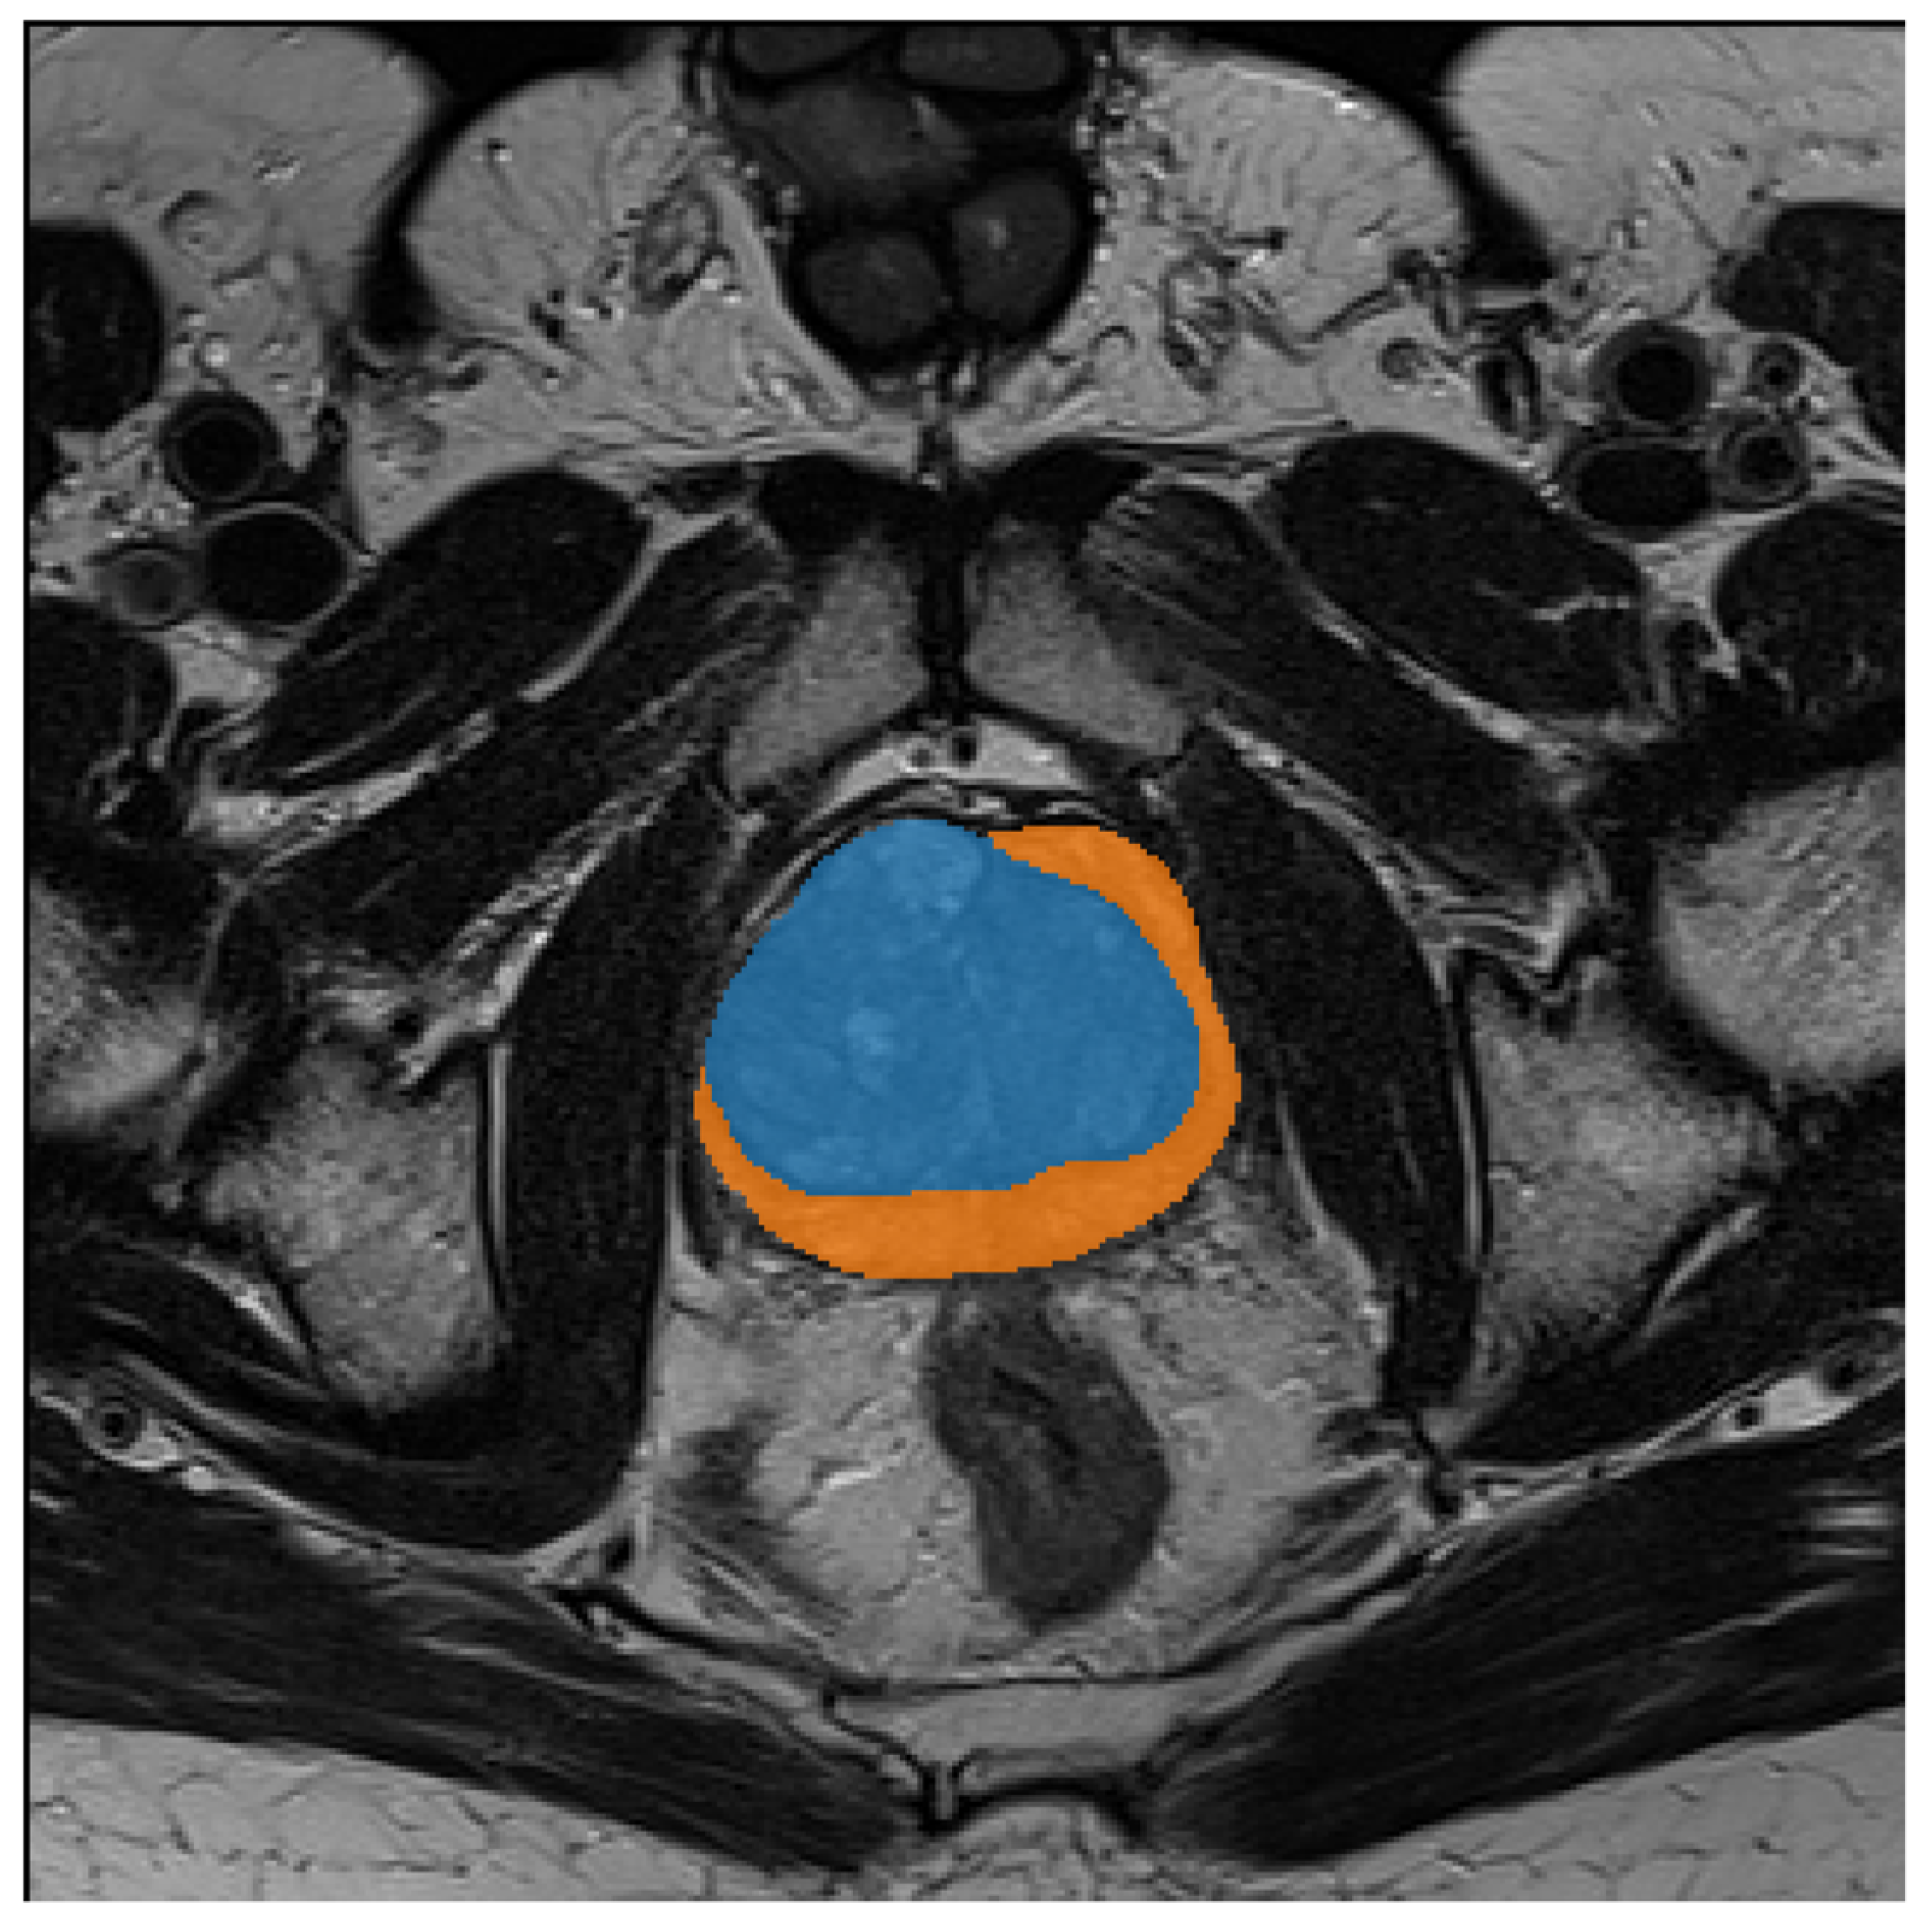

2.1. Prostate MRI Dataset

2.2. Texture Analysis